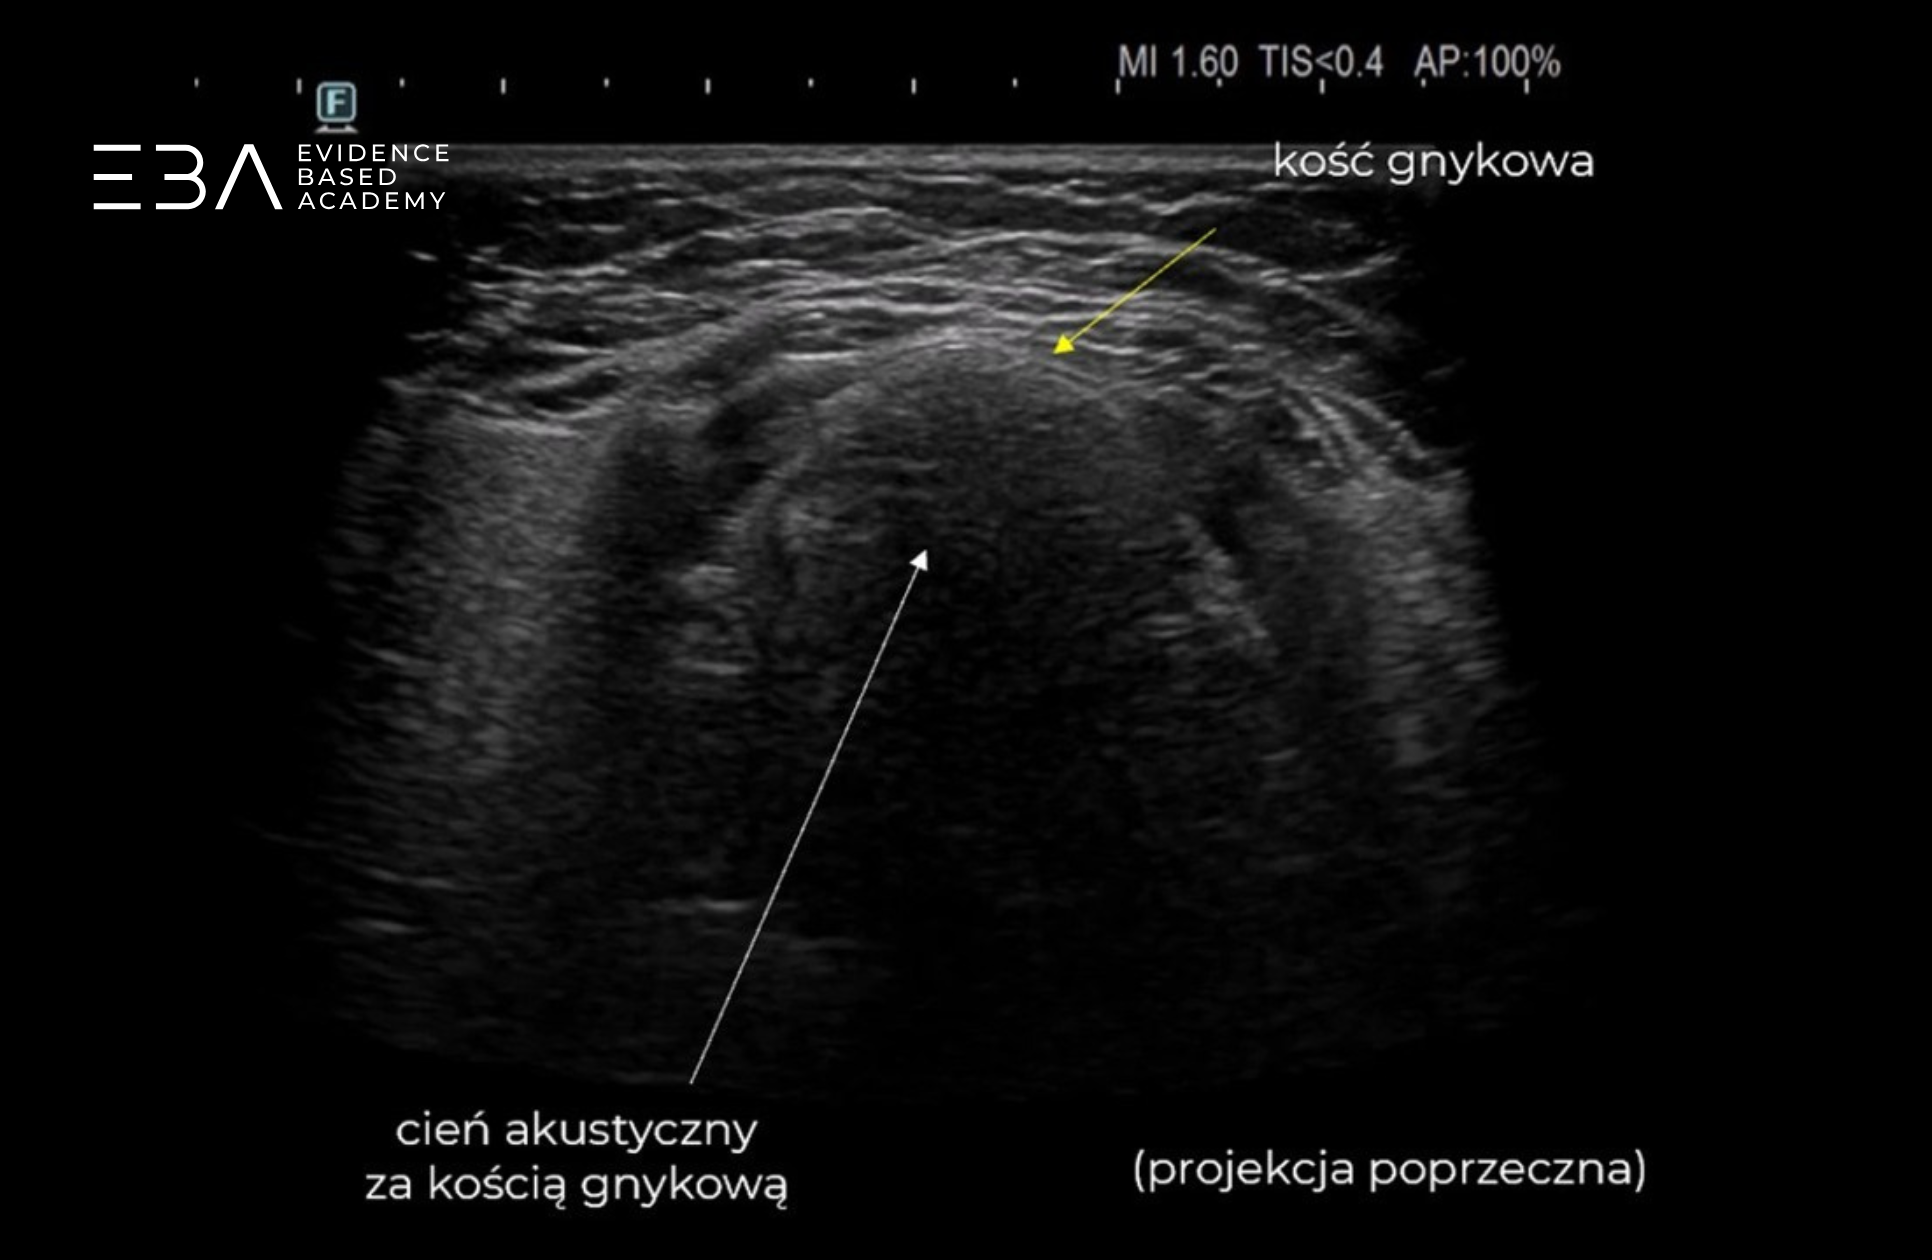

Okolica kości gnykowej – projekcja poprzeczna i podłużna.